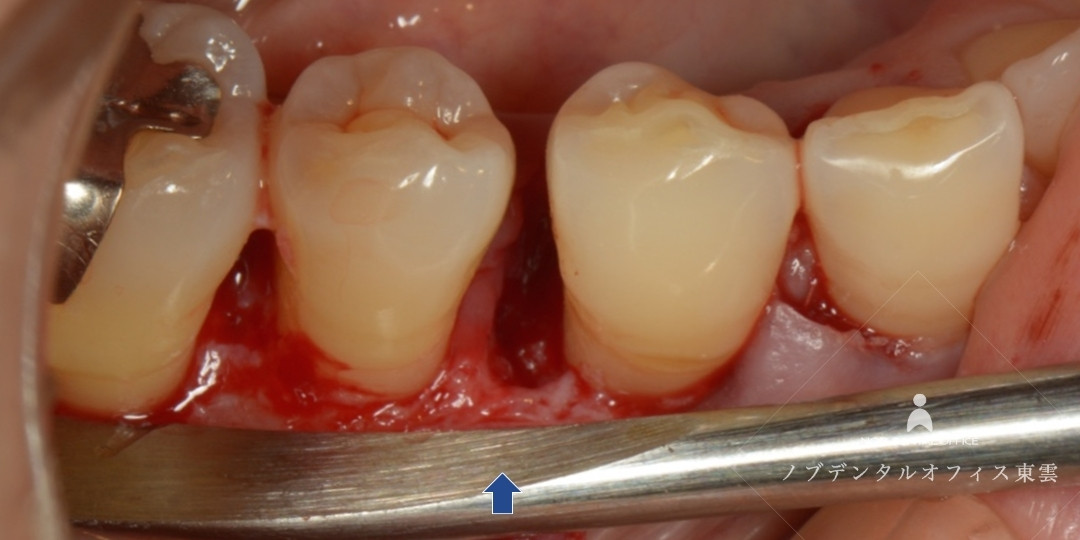

歯周基本治療をした後の写真。歯ぐきが引き締まりました。

リグロスを用いた歯周組織再生療法の様子。

歯周組織再生療法では、汚れている部分を徹底的に除去し、リグロスと骨補填材を使用して、歯周再生療法を行いました。

汚れている部分を除去している様子

リグロスと骨補填材をセットした様子

歯ぐきがひきしまり、しっかり歯をおおっています。この後セラミック治療を行いました。